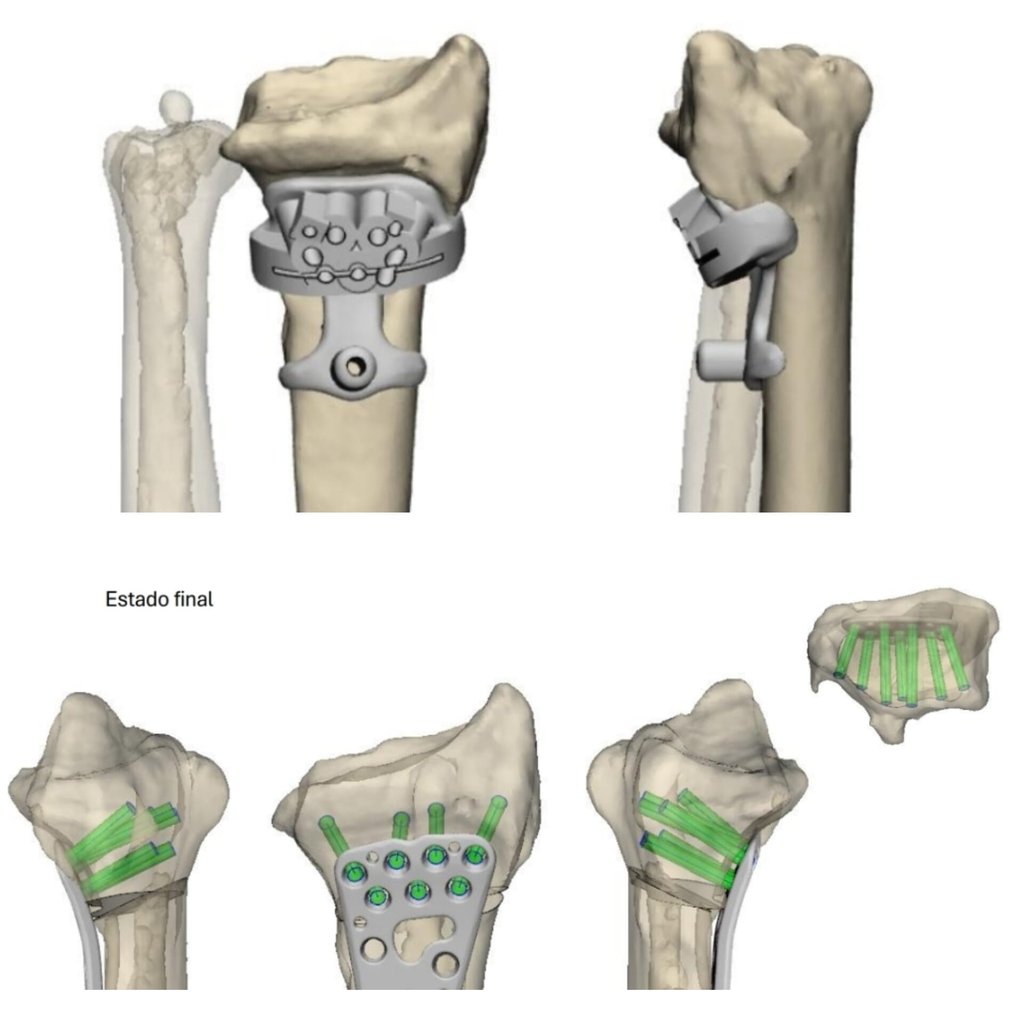

Planificación con impresión 3D